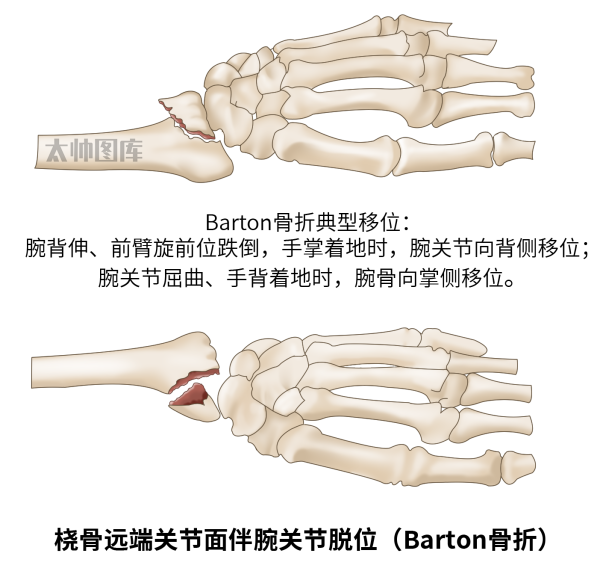

桡骨远端关节面骨折伴腕关节脱位(Barton骨折):是桡骨远端骨折的一种特殊类型。在腕背伸、前臂旋前位跌倒,手掌着地时,桡骨关节背侧发生骨折,腕关节向背侧移位;在跌倒时,腕关节屈曲、手背着地受伤,可发生桡骨远端掌侧关节面骨折,腕骨向掌侧移位。